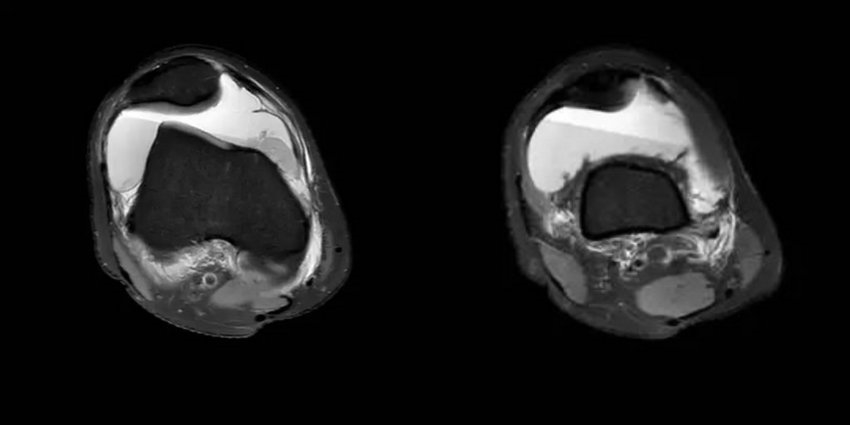

小赵女士在一次外出游玩时扭伤右膝关节,顿感膝关节疼痛不适,“打软腿”,就诊于当地医院CT检查提示关节积液。经熟人介绍来郑州大学五附院骨科一病区就诊,经主管医师张鹏飞仔细查体后,发现膝关节浮髌试验阳性,右侧髌骨内侧压痛,髌骨外推试验(+),恐惧试验(+),J-sign(+)。完善MRI等相关检查(见图1),证实为内侧副韧带(MPFL)完全撕裂。仔细追问病史,患者诉既往曾有过数次髌骨外移的症状,经休息后缓解,患者复发性髌骨脱位诊断明确。

图1 术前MRI检查